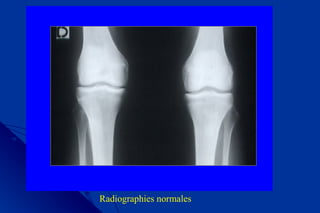

3/Arthrose fémoro-tibiale : signes radiologiques3/Arthrose fémoro-tibiale : signes radiologiques

• Clichées de face debout en extension, en semi-flexionClichées de face debout en extension, en semi-flexion

• Cliché de profil en semi flexionCliché de profil en semi flexion

Radiographies normales